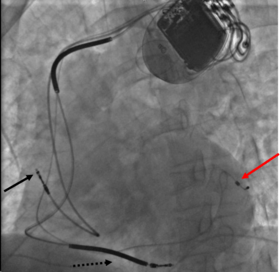

Biventricular pacing

Cardiac resynchronization therapy (CRT) is used for people with heart failure in whom the left and right ventricles do not contract simultaneously (ventricular dyssynchrony), which occurs in approximately 25–50% of heart failure patients. To achieve CRT, a biventricular pacemaker (BVP) is used, which can pace both the septal and lateral walls of the left ventricle. By pacing both sides of the left ventricle, the pacemaker can resynchronize the ventricular contractions.

CRT devices have at least two leads, one passing through the vena cava and the right atrium into the right ventricle to stimulate the septum, and another passing through the vena cava and the right atrium and inserted through the coronary sinus to pace the epicardial wall of the left ventricle. Often, for patients in normal sinus rhythm, there is also a lead in the right atrium to facilitate synchrony with the atrial contraction. Thus, timing between the atrial and ventricular contractions, as well as between the septal and lateral walls of the left ventricle can be adjusted to achieve optimal cardiac function.

Biventricular pacing alone is referred to as CRT-P (for pacing). For selected patients at risk of arrhythmias, CRT can be combined with an implantable cardioverter-defibrillator (ICD): such devices, known as CRT-D (for defibrillation), also provide effective protection against life-threatening arrhythmias.[39]